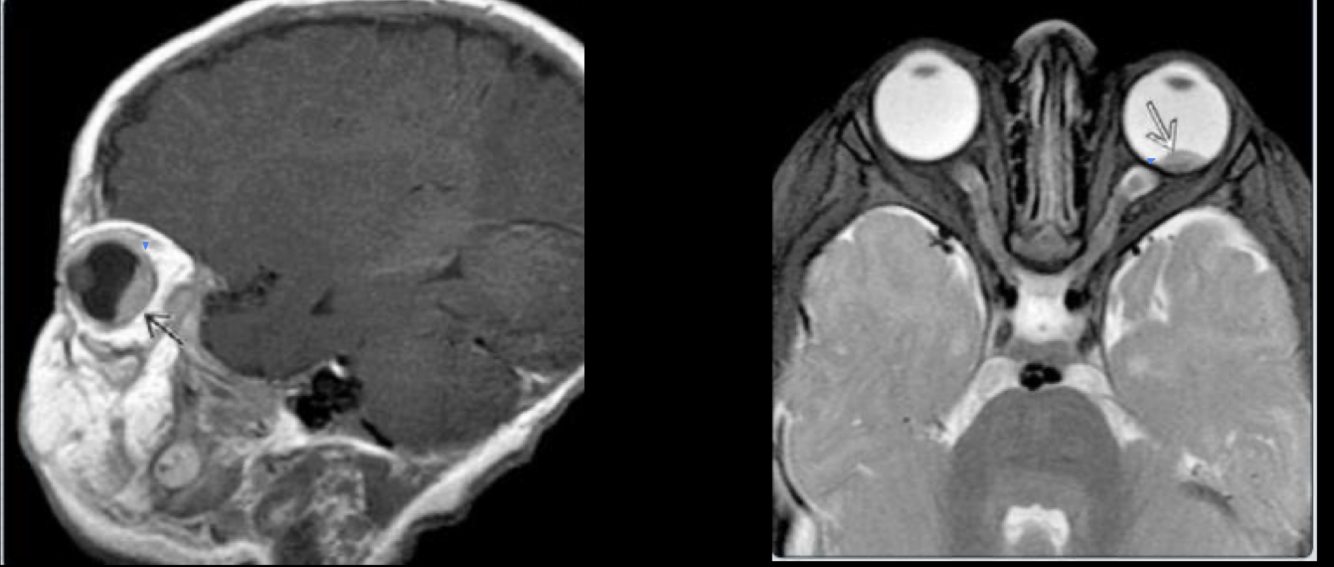

RB trilateral

Evaluar implicaciones intra

y extra oculares así como

intracraneales

Se puede identificar hemorragia

retinal

Mejor caracterizacion de lesion

pineal